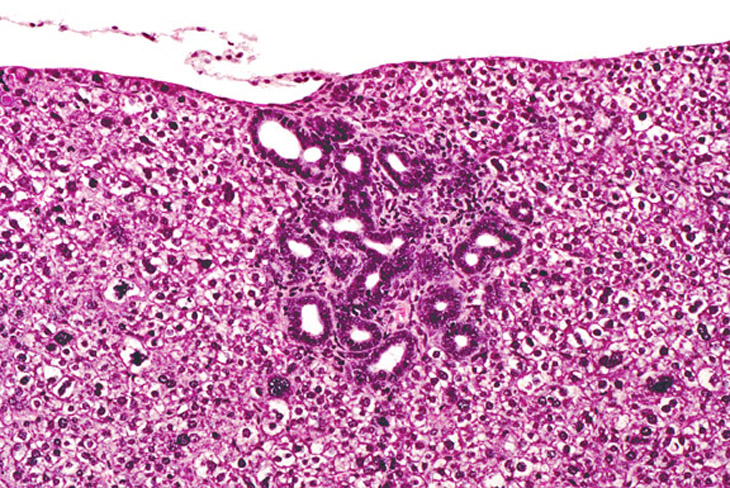

Bile duct proliferation in a 4-week old AL-TAg mouse. Some surrounding hepatocytes are dysplastic